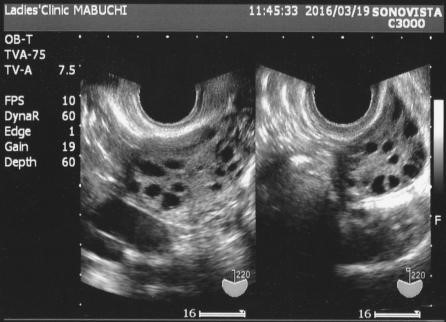

• 一方または両方の卵巣の嚢胞

• 超音波:超音波は卵巣と子宮の画像を作成します。